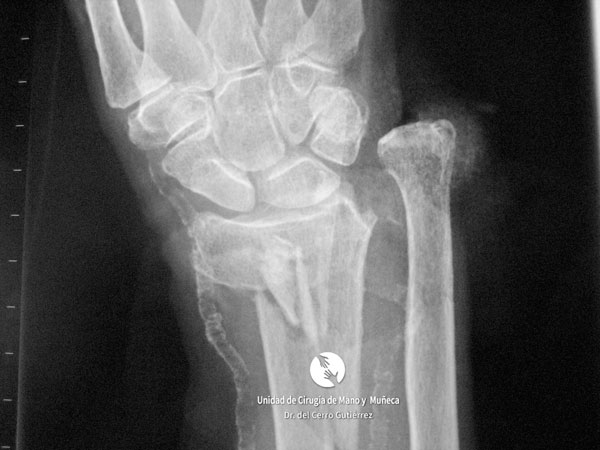

Imágenes de diagnótico de fracturas del radio distal de la muñeca

Fractura del Radio. Avulsión Estiloides.

Fractura del Radio. Desplazamiento Dorsal.

Fractura del Radio. Fractura Extraarticular

Fractura del Radio.

Fractura del Radio. Fractura del Escafoides.

Fractura del Radio. Conminuta y Articular.